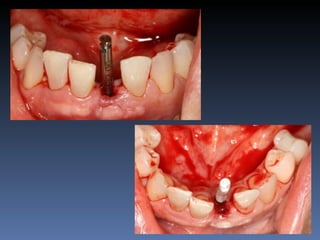

BOX 4

Ville Victorazzo Carmo

Idade – 20 anos

Sexo – Masculino

Raça – Caucasiana

ASA – I

Data- 27-04-2012

Diagnóstico: Desdentado da zona 2.1,

pré-regenerada.

Plano de tratamento: Instalação de implante endo-

ósseos ( 2.1 ) para reabilitação protética fixa.